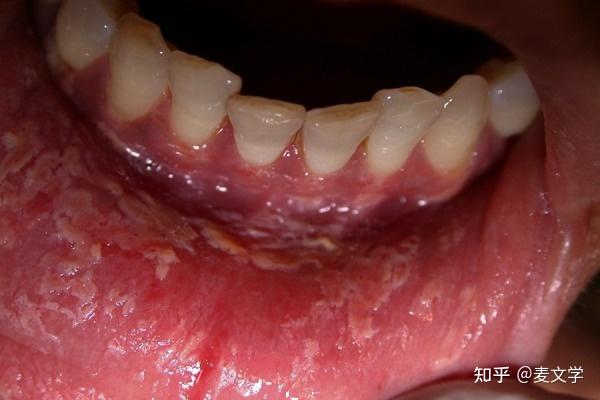

【求助】口腔黏膜病变 - 口腔 -丁香园论坛